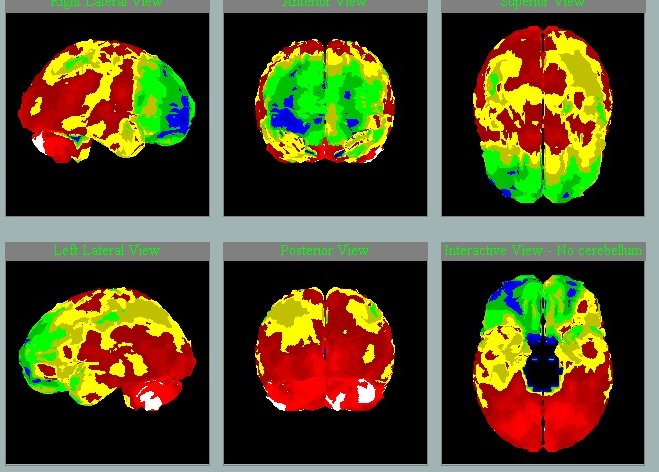

Perfúze při neurodegenerativním onemocnění mozku

V letech je možné vidět přibývání hypoperfúze a tedy progresi:

2011

2014

2020